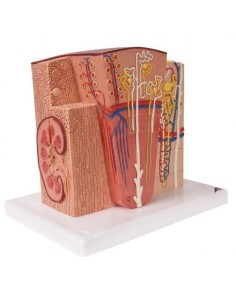

Dal cranio in 22 parti con incastri magnetici ai modelli di colonna vertebrale, da quelli di articolazioni a quelli di cuore, ogni pezzo della nostra collezione è progettato per un’immersione totale nello studio dell’anatomia umana. I nostri modelli, realizzati tramite scansioni di ossa vere, garantiscono un’esperienza tattile autentica e una fedeltà di peso quasi identica agli originali.